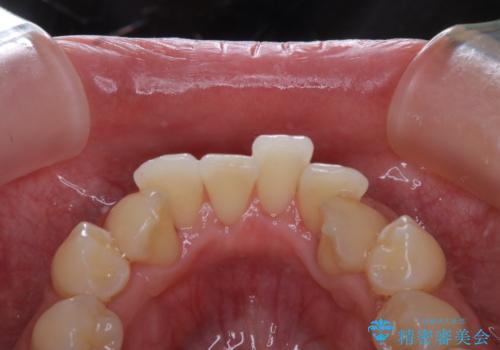

矯正治療が始まる前に歯磨きチェックとクリーニング

- 矯正治療がまもなくスタートするため、きれいにしたいのと歯磨きを上達したいとのことでした。染め出しをしての歯磨きチェック・指導とPMTC30分コースを行いました。

染め出し液を使ってプラークを染め出すことにより、普段の歯みがきで磨き残している場所を目で確かめることができます。

日々の歯磨きを上達するには、まずどこが磨けていないか認識することが大切です。